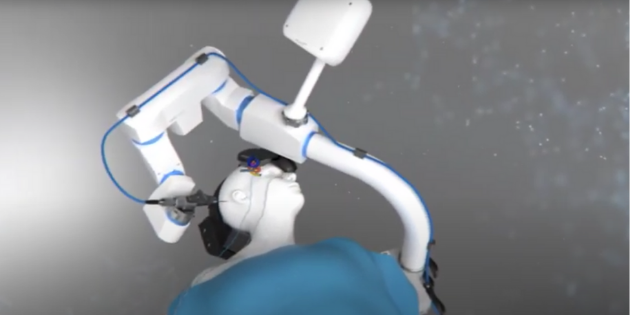

Deux interventions chirurgicales, destinées à implanter des patients, ont récemment été réalisées à l’aide d’un...